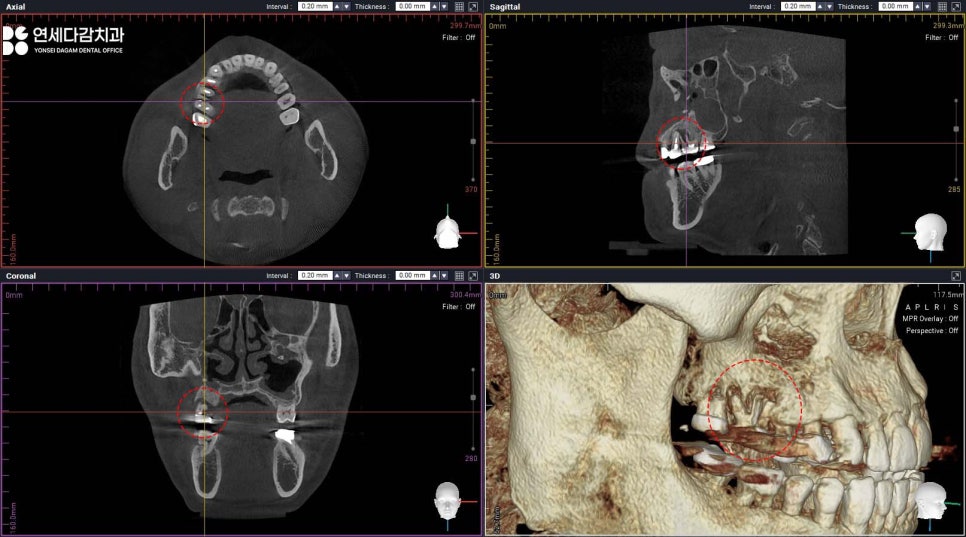

따라서 이러 경우 CT 분석을 통해

사용할 수 있는 뼈를 미리 정확히 확인하고,

필요한 경우 추가적인 골이식술을

동반하여 진행해야 됩니다.

송파구 치과 에서는 이렇게 다양한 각도로

3차원적으로 구조를 살펴보며

염증의 범위를 살펴봅니다.

또한 결손 부위를 피해 가능한

건강한 골조직에 위치하도록

신중하게 각도와 깊이를 계획하고,

적절한 크기와 길이의

인공 치근(Fixture)을 선택하였습니다.